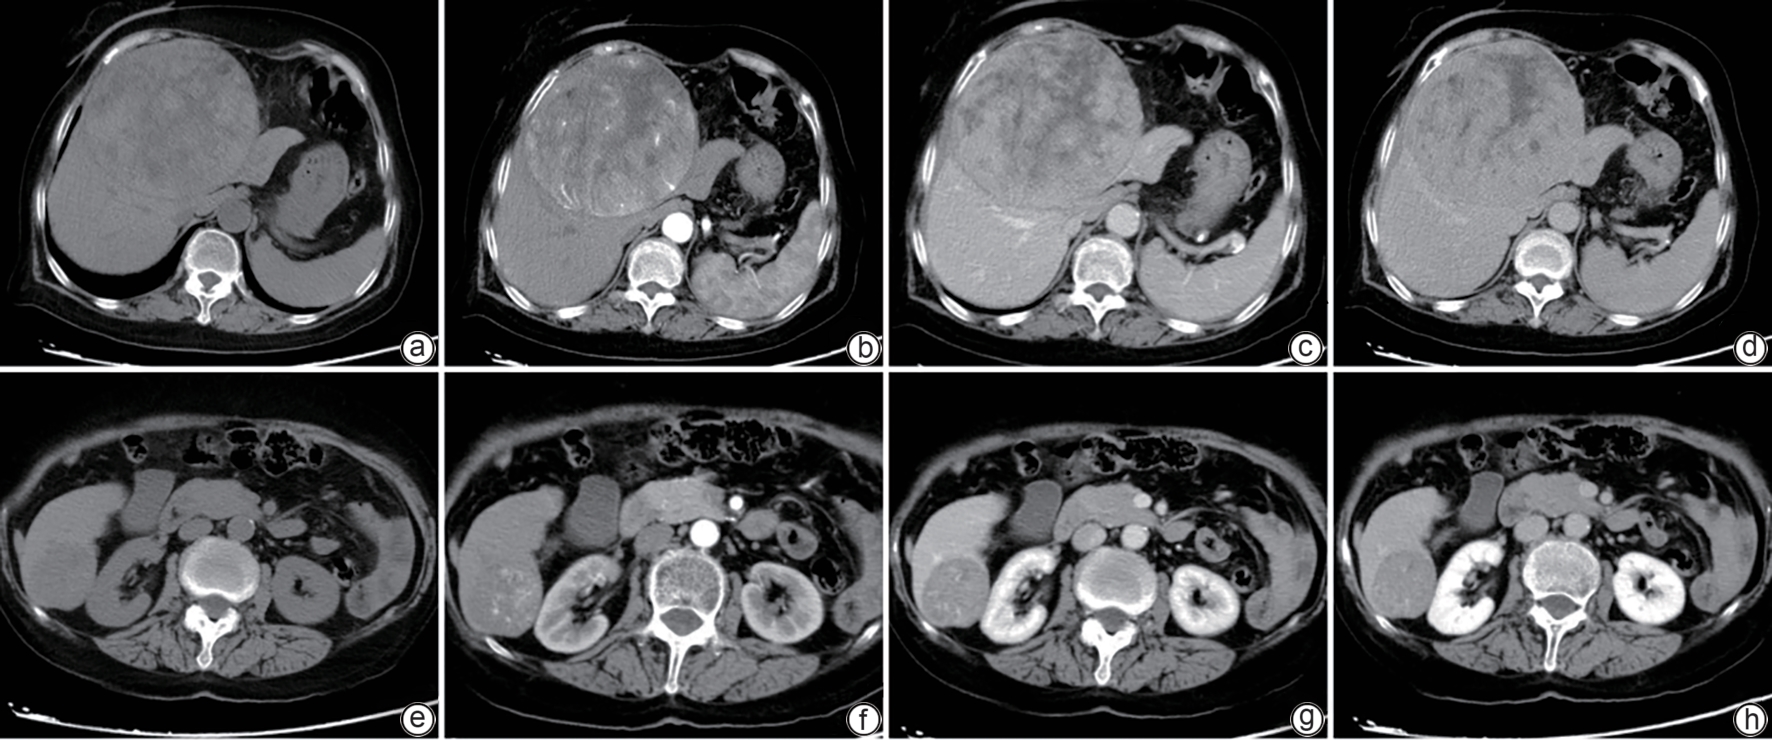

Liver Fibrosis and Liver Cirrhosis

Clinical and pathological features of patients with congenital hepatic fibrosis: An analysis of 26 cases

Shixuan LIU, Yujiao ZHANG, Ying ZHENG, Aiping SONG, Tailing WANG, Xiuhong WANG

2025, 41(11): 2317-2322. DOI: 10.12449/JCH251118

Abstract(102) HTML (25) PDF (2080KB)(43)

Abstract:

Objectives  To summarize the clinical and pathological features of patients with congenital liver fibrosis (CHF), and to investigate the differences in clinical and pathological features between patients in different age groups.  Methods  A retrospective analysis was performed for the clinicopathological data of 26 patients with pathologically confirmed CHF in China-Japan Friendship Hospital from August 2005 to June 2023, and the patients were stratified by age to investigate the clinical and pathological features of patients in different age groups.  Results  Among the 26 patients, there were 12 male patients and 14 female patients, with an age of onset of 4 — 61 years. There were 19 patients with portal hypertension type (73.08%), 2 patients with cholangitis type (7.69%), 4 patients with mixed type (15.38%), and 1 patient with occult type (3.85%). Of all 26 patients, 4 had unknown clinical symptoms, and among the 22 patients with clear clinical symptoms, 10 (45.45%) attended the hospital due to upper gastrointestinal bleeding caused by portal hypertension. Pathological manifestations included roughly normal liver parenchyma separated by fibrous septa in the portal area, with the presence of abnormal reactive bile duct hyperplasia. Denser fibrous septa and a lack of portal veins with the corresponding caliber were observed in 4 pediatric patients with disease onset before the age of 10 years, with a significant reduction or even disappearance of compensatory thin-walled blood vessels.  Conclusion  Portal hypertension-type CHF is the most common type in clinical practice. Patients with an early age of onset have certain histopathological features of the liver, with the presence of serious complications associated with portal hypertension. Therefore, liver biopsy should be performed for patients suspected of CHF in clinical practice, and genetic testing should be performed when necessary. Early identification and diagnosis are of great importance for improving the prognosis of patients.